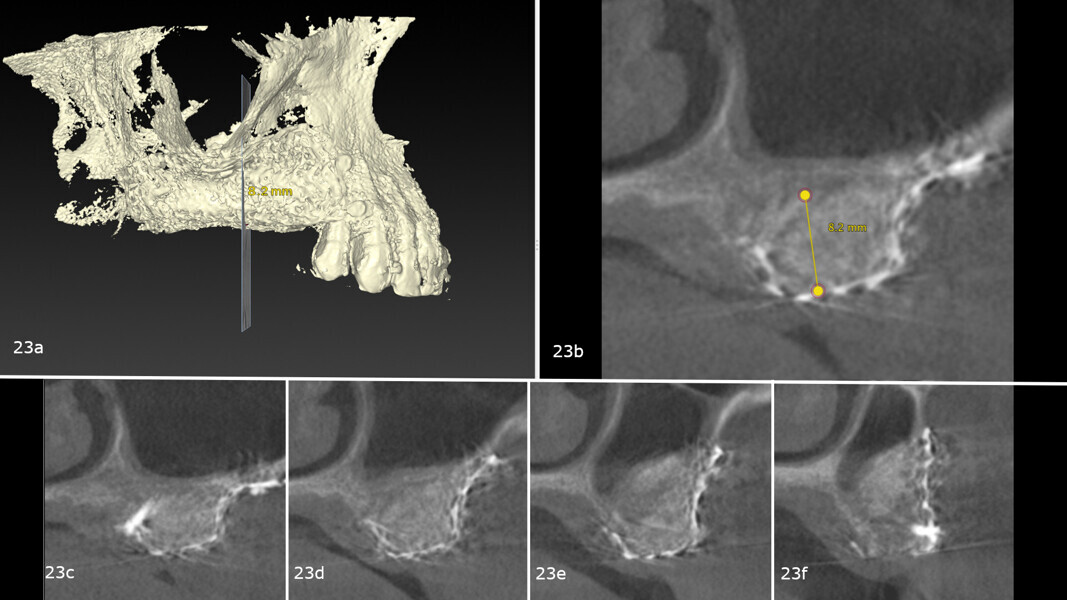

After nine months, a second CBCT scan was performed to assess the regenerated bone volume and plan the computer-guided surgery (Figa. 23a-f). The STL files obtained from the intra-oral scan, and the DICOM files from the CBCT scan were used to plan implant placement through computer-guided surgery (naviMAX, Biomax; Figs. 24a-d).